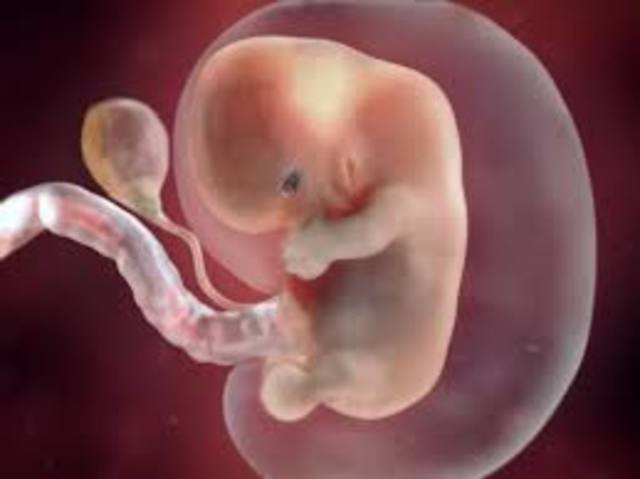

Embryo- A unborn offspring in the process of development, during the period from approximately the second to the eighth week after fertilization.

• 2nd Month

2nd Month

6 weeks:

1. 5/8 inches long.

2. Eyelids form.

3. All organs developed.

8 weeks:

1. Bones and muscles developing.

2. Leg buds start to grow.

3. Arm buds start to grow.